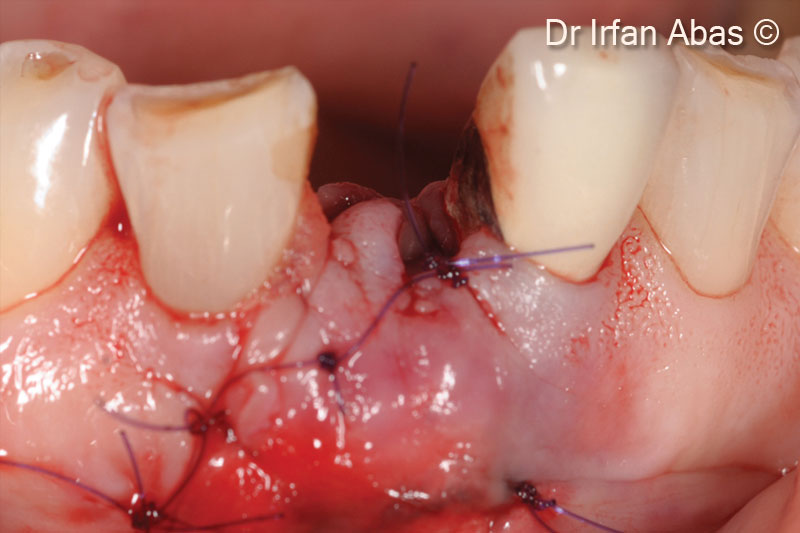

9. The flap is sutured

10. Occlusal view of the suture